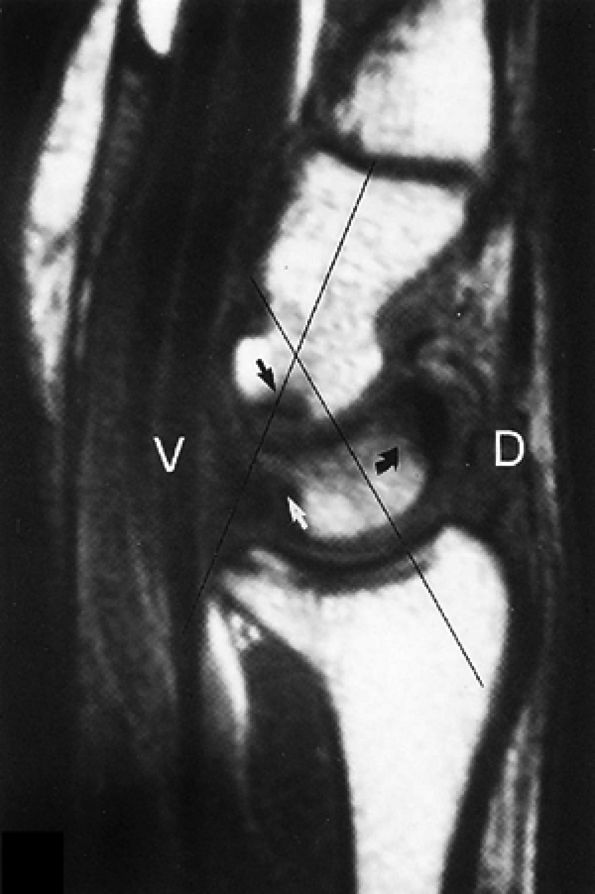

FIGURE 10.89 ● (A) DISI with dorsal tilting of the lunate (curved arrow) without volar shift. Note the dorsal displacement of the capitate relative to the radius. The capitolunate angle (double-headed arrow) measures 32°. (B) Palmar tilting of the scaphoid (curved arrow) causes an abnormally increased scapholunate angle (double-headed arrow) of 124°. D, dorsal; V, volar.